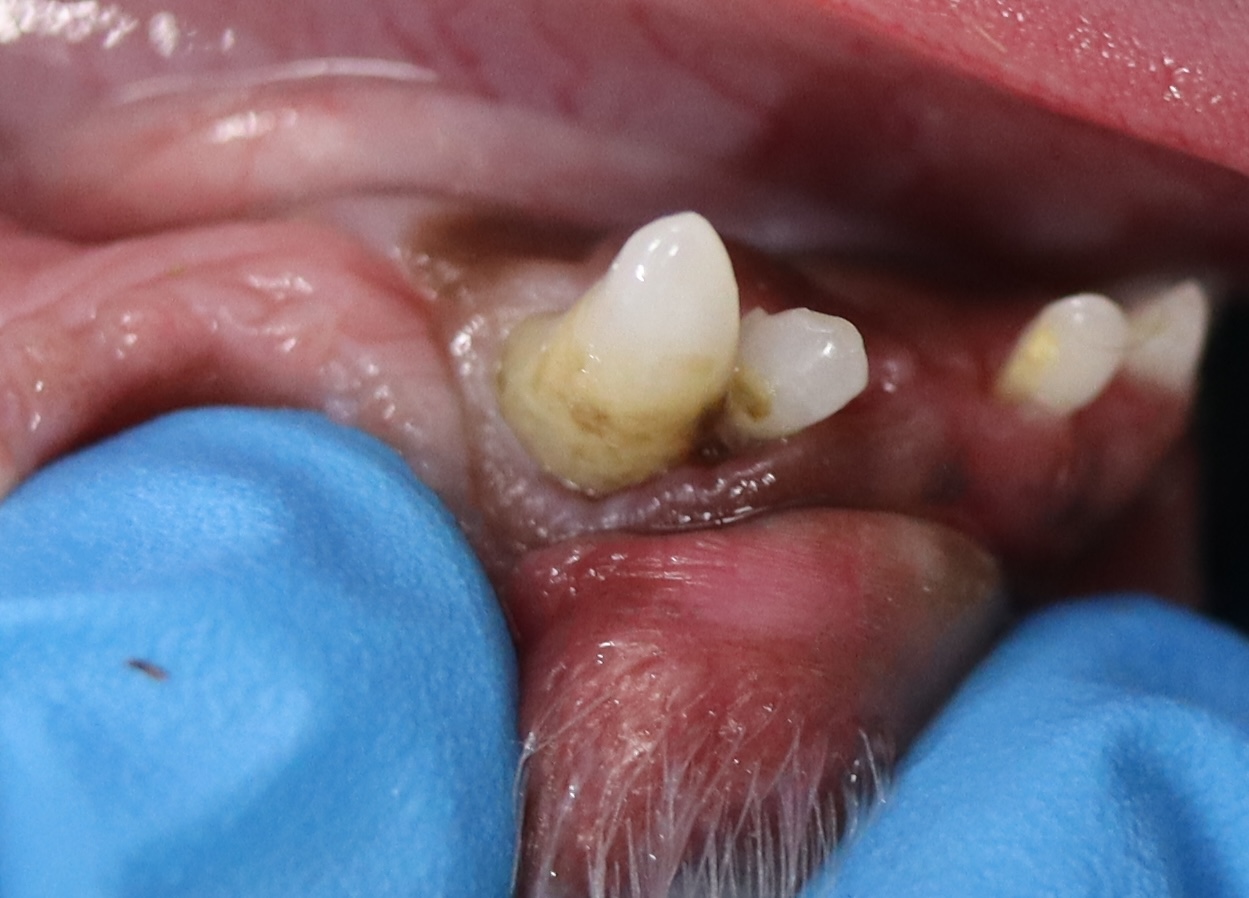

犬・猫の破折歯

犬は奥歯(第四前臼歯)、猫は牙(犬歯)が折れやすいと言われています。ハサミで切れないような硬いものを噛む習慣がある場合、必ず確認しましょう。

歯が折れてしまった場合、抜歯もしくは歯を温存する歯内治療が必要になります。

折れた歯も状況によっては温存することは可能ですのでご相談ください。